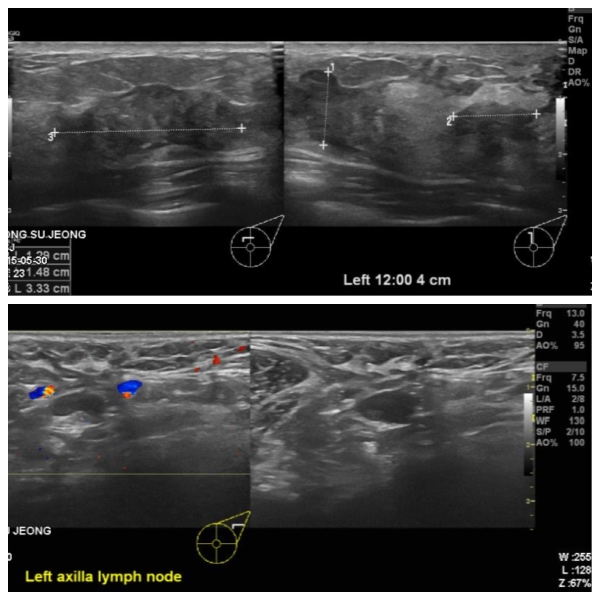

건강 검진상 이상 소견으로 내원하신 40대 여성분으로 유방초음파 실시하여

좌측 유방에 12 :00 방향에서 4cm 떨어진 거리의 의심스러운 혹 조직검사와 겨드랑이

림프절에 의심되는 혹 세표검사  시행하였고, 좌측 침윤성 유관암과 겨드랑이 전이 진단

되었습니다.